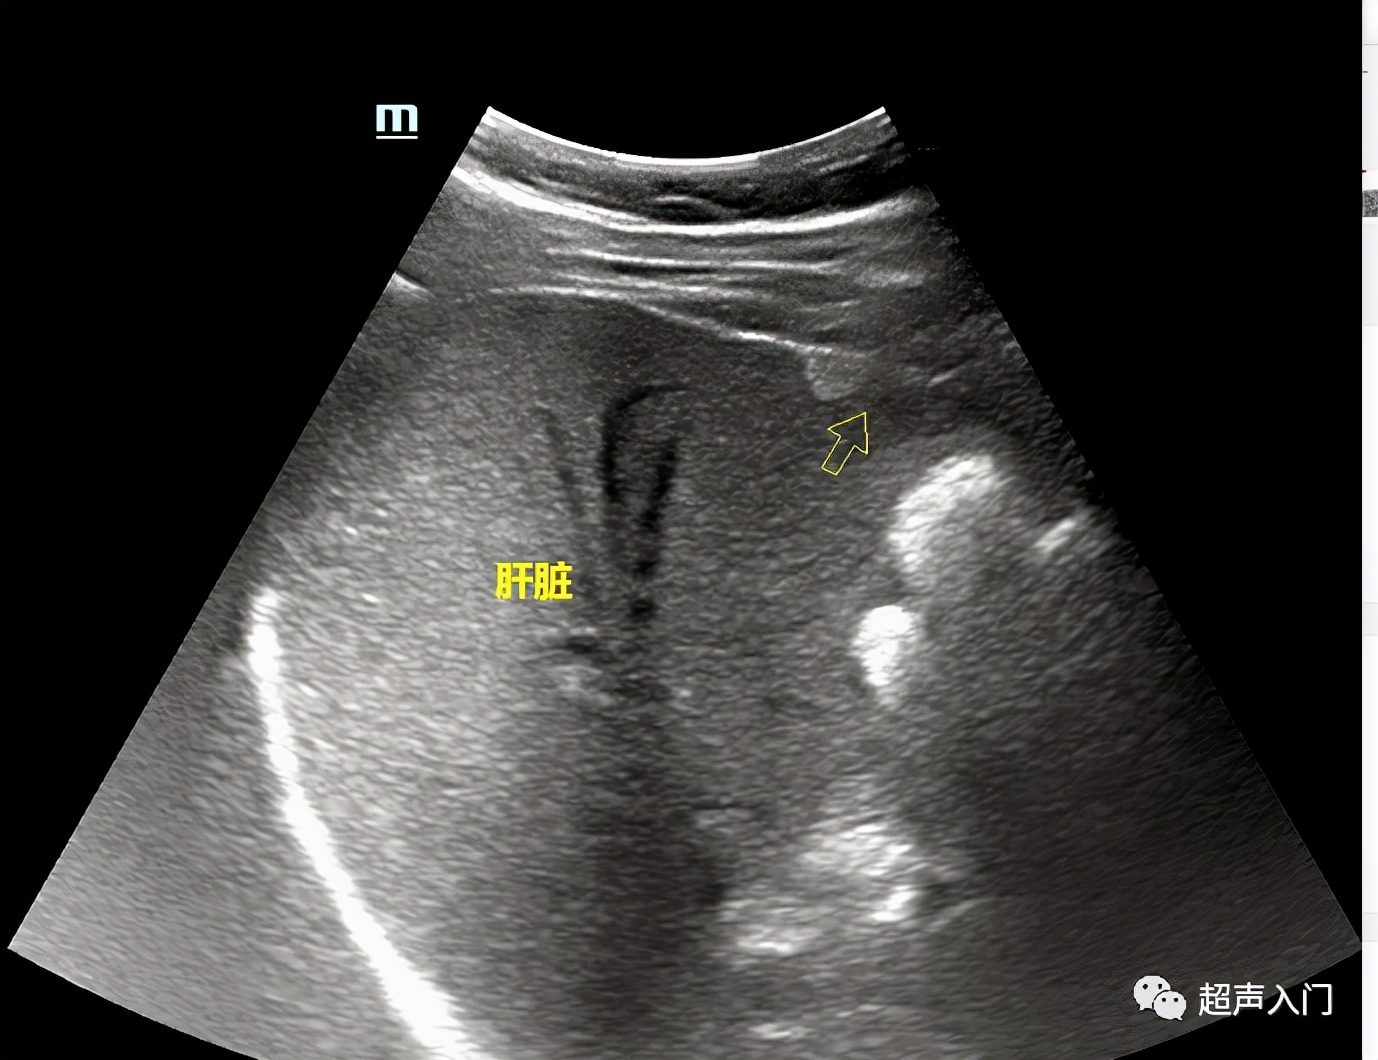

03 肝内血管瘤

(箭头前面那个白团团)

05 肝内胆管扩张

(著名的“平行管”征)